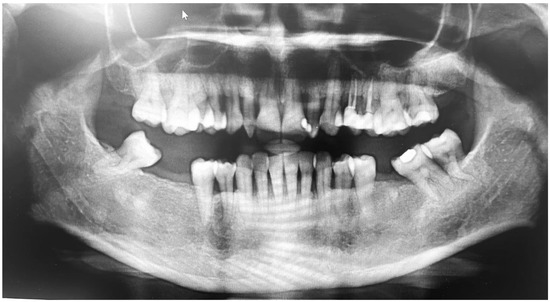

Extraoral examinations were within normal limits, focusing on facial symmetry, temporomandibular joint (TMJ), and potential trigger points of trigeminal neuralgia (TN). Upon intraoral examination, the patient had localized gingival inflammation in the upper and lower anterior areas, with punched-out papillae similar to necrotizing uncreative gingivitis (NUG). There was gingival recession of 2–7 mm, along with visible plaque and calculus in the same area and associated halitosis (Figure 3A–D). However, the pocket depth was not recorded due to severe pain upon touch, with a score of 9 out of 10 measured on the visual analog scale (VAS). Active dental caries at #16, 17 and previous restorations at teeth #24, 25, 37 were also observed (Figure 4).

During the subsequent visit after 1 week, the aim was to further reduce the bacterial load. Accordingly, full-mouth ultrasonic scaling with light supra-gingival scaling only at the anterior teeth was performed under topical anesthesia with OHI re-enforcement, as she continued to complain of pain when the gingiva were touched. On visual analogue scale, the patient had a scoring of 4 out of 10. The Ainmo and Bay bleeding index (BI) was 76%, with mobility of grade III at #31, #32, #41, and #42, grade II at #12, #22, and grade 1 at #11, #21, #33, and #43, with probing pocket depth (PPD) average of ≥5 mm in more than 30% of the sites involved. Furthermore, the clinical attachment loss was ≥5 mm #31, #32, #41, #42, #12, #13, #21, and #22. With the above description, the case was diagnosed as stage III and grade B periodontitis.

On the first follow-up visit after 1 month, the bleeding index was reduced to 15%, with a normal pale pink color of the gingiva and better consistency, clinical attachment loss (CAL) #11, #21, #13, #23, #33, #43 ranging between (2–4 mm), mobility of grade 1 at #11, #21, and PD from 6 mm to 3 mm with reduced but stable periodontium. Initially, restorations were conducted in #16, #17, followed by open flap debridement in relation to #25, #26 and #37, #38. Later, fiber splinting was conducted in the lower anterior (33–43). Lastly, implants were placed in #36, #46, and #47.

Figure 4. Orthopantomogram showing generalized horizontal bone loss, multiple missing teeth, and restorations.